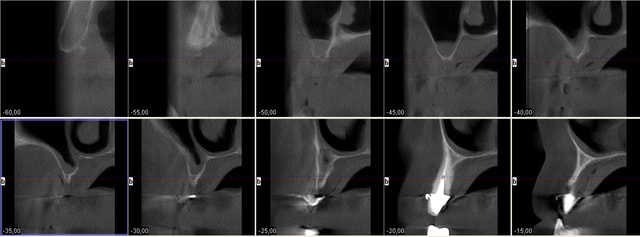

Au maxillaire il faut faire une implanto totale et stt ne pas garder les canines

A la mandibule faut disker mais ça va

PS il faut d abord faire réaliser des modèles stéréolithographiques par Materialise pour se prononcer au final

Mais c est un joli cas ;-)))))))))

Cas promis... à dentiste 57 et à growler... le voici

Pour Pluton aussi ;-))))

Bon je cesse la liste sinon je vais créer un ordre de préséance entre vous , ordre malvenu sans doute ;-)))

Pp